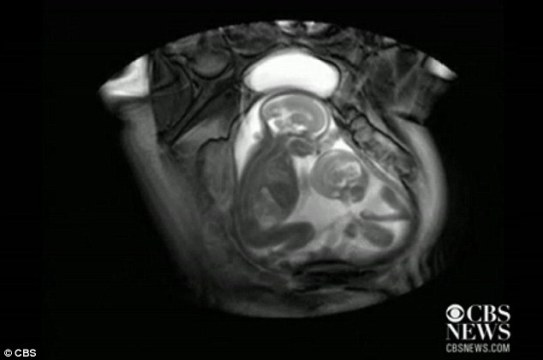

据外媒报道,近日一段对孕期20周孕妇的核磁共振的扫描视频显示,一对双胞胎还在妈妈肚子里就开始挥动手脚 “掐架”,令人感到神奇又搞笑。

据报道,英国伦敦帝国理工学院(Imperial College)胎儿保健中心本打算用核磁共振成像仪来诊断共享一个胎盘和同一个血液供应系统的胎儿双胞胎输血症候群(twin transfusion syndrome)情况,却意外拍到了子宫中双胞胎的“大战”。

视频显示,画面右边个子稍小的胎儿在对左边稍大的胎儿挥动手脚,“拳打脚踢”,似乎打算用身体争得更多空间。而后者比较安分,也动了动嘴,缩了一下身子。